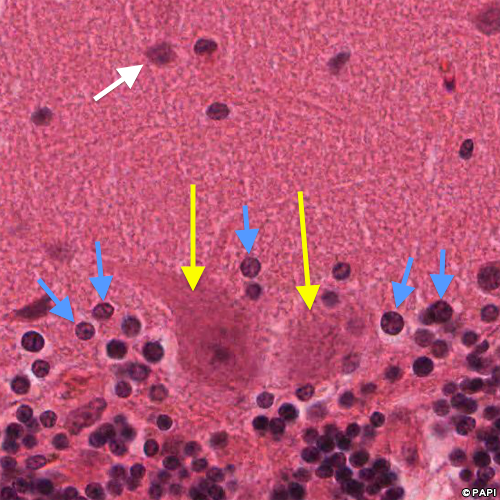

Yellow arrows indicate the Purkinje cells. Blue ones indicate the nuclei of the Bergmann glia, which is the astrocyte in the Purkinje cell layer. A white arrow points the basket cell in the molecular layer.